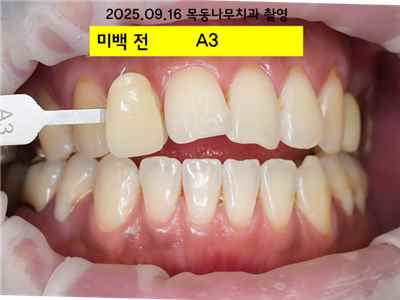

치아 변색 외부 요인